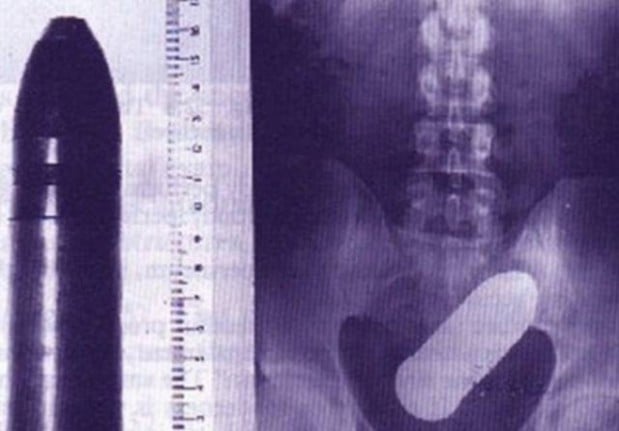

#12 Tykin panos